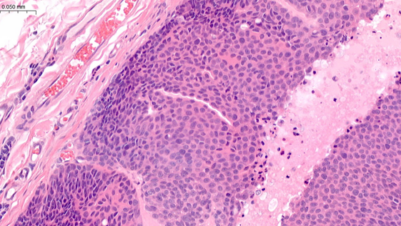

NationWide Laboratories are committed to making a positive impact on animal health by offering innovative products, technology and laboratory services to your veterinary practice. They have been providing a comprehensive range of veterinary diagnostic services since 1983. Their expert teams can assist you in making decisions on relevant testing for companion, exotic and farm animals. They offer full interpretation in a range of testing areas including biochemistry, haematology, cytology, histopathology, endocrinology, microbiology, etc. Their sample collection service is powered by National Veterinary Services.